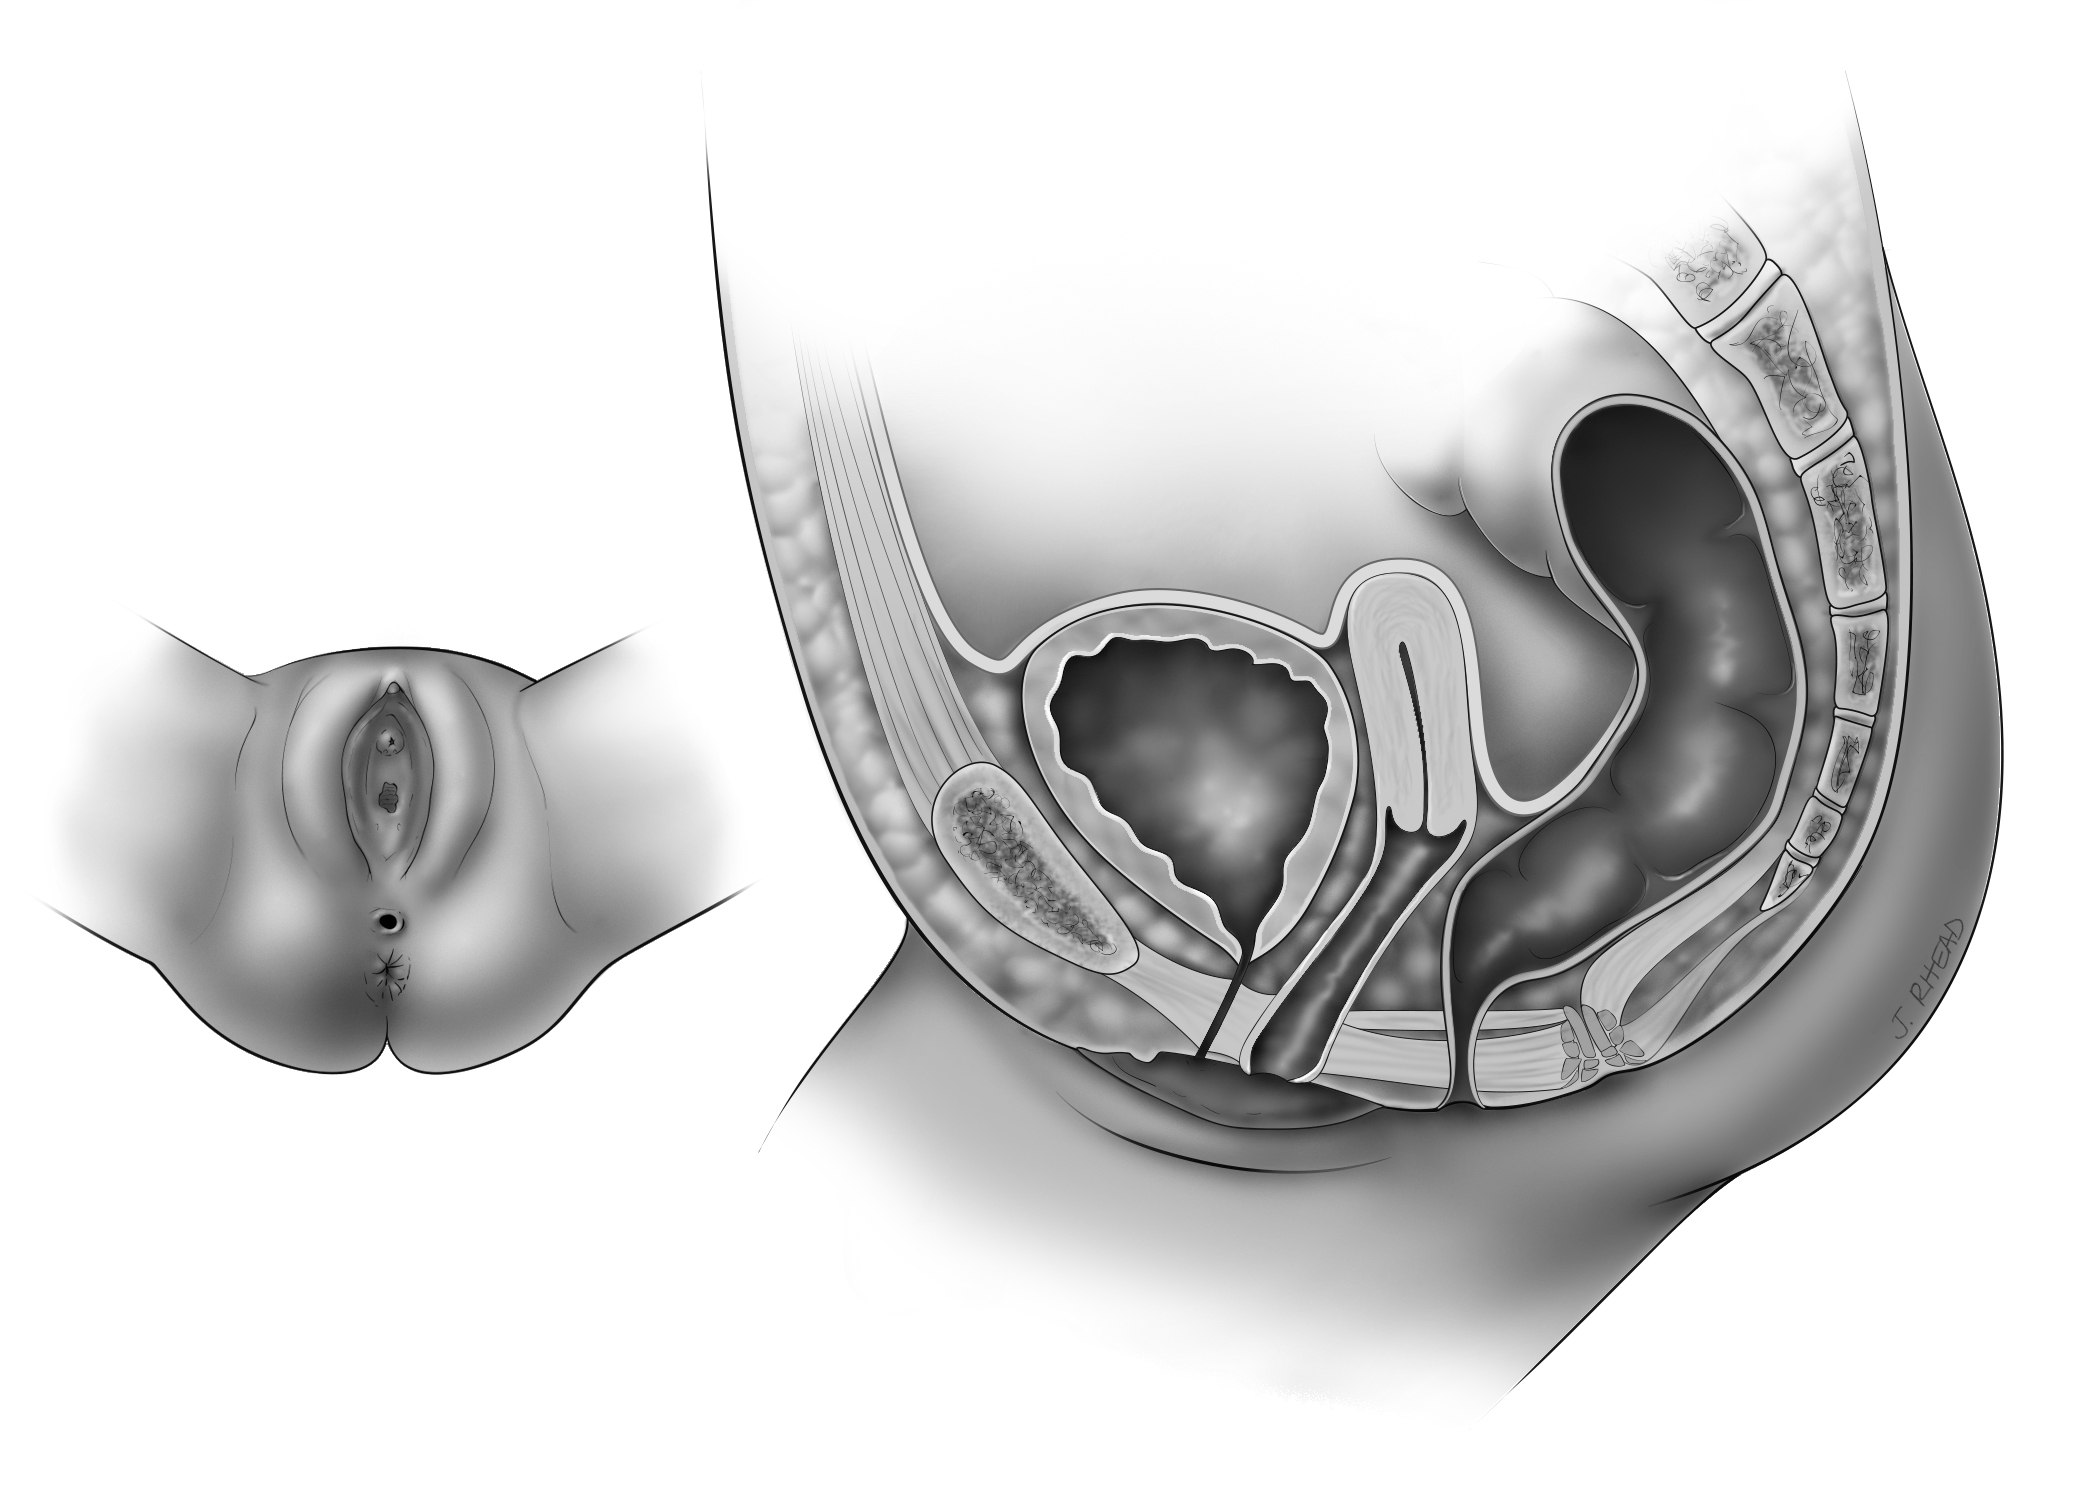

Perineal Fistula

The anus is located in front of where the anus is normally placed or is too small

Vestibular Fistula

The rectum opens just behind the vagina (the space between the vaginal hymen and perineal skin).